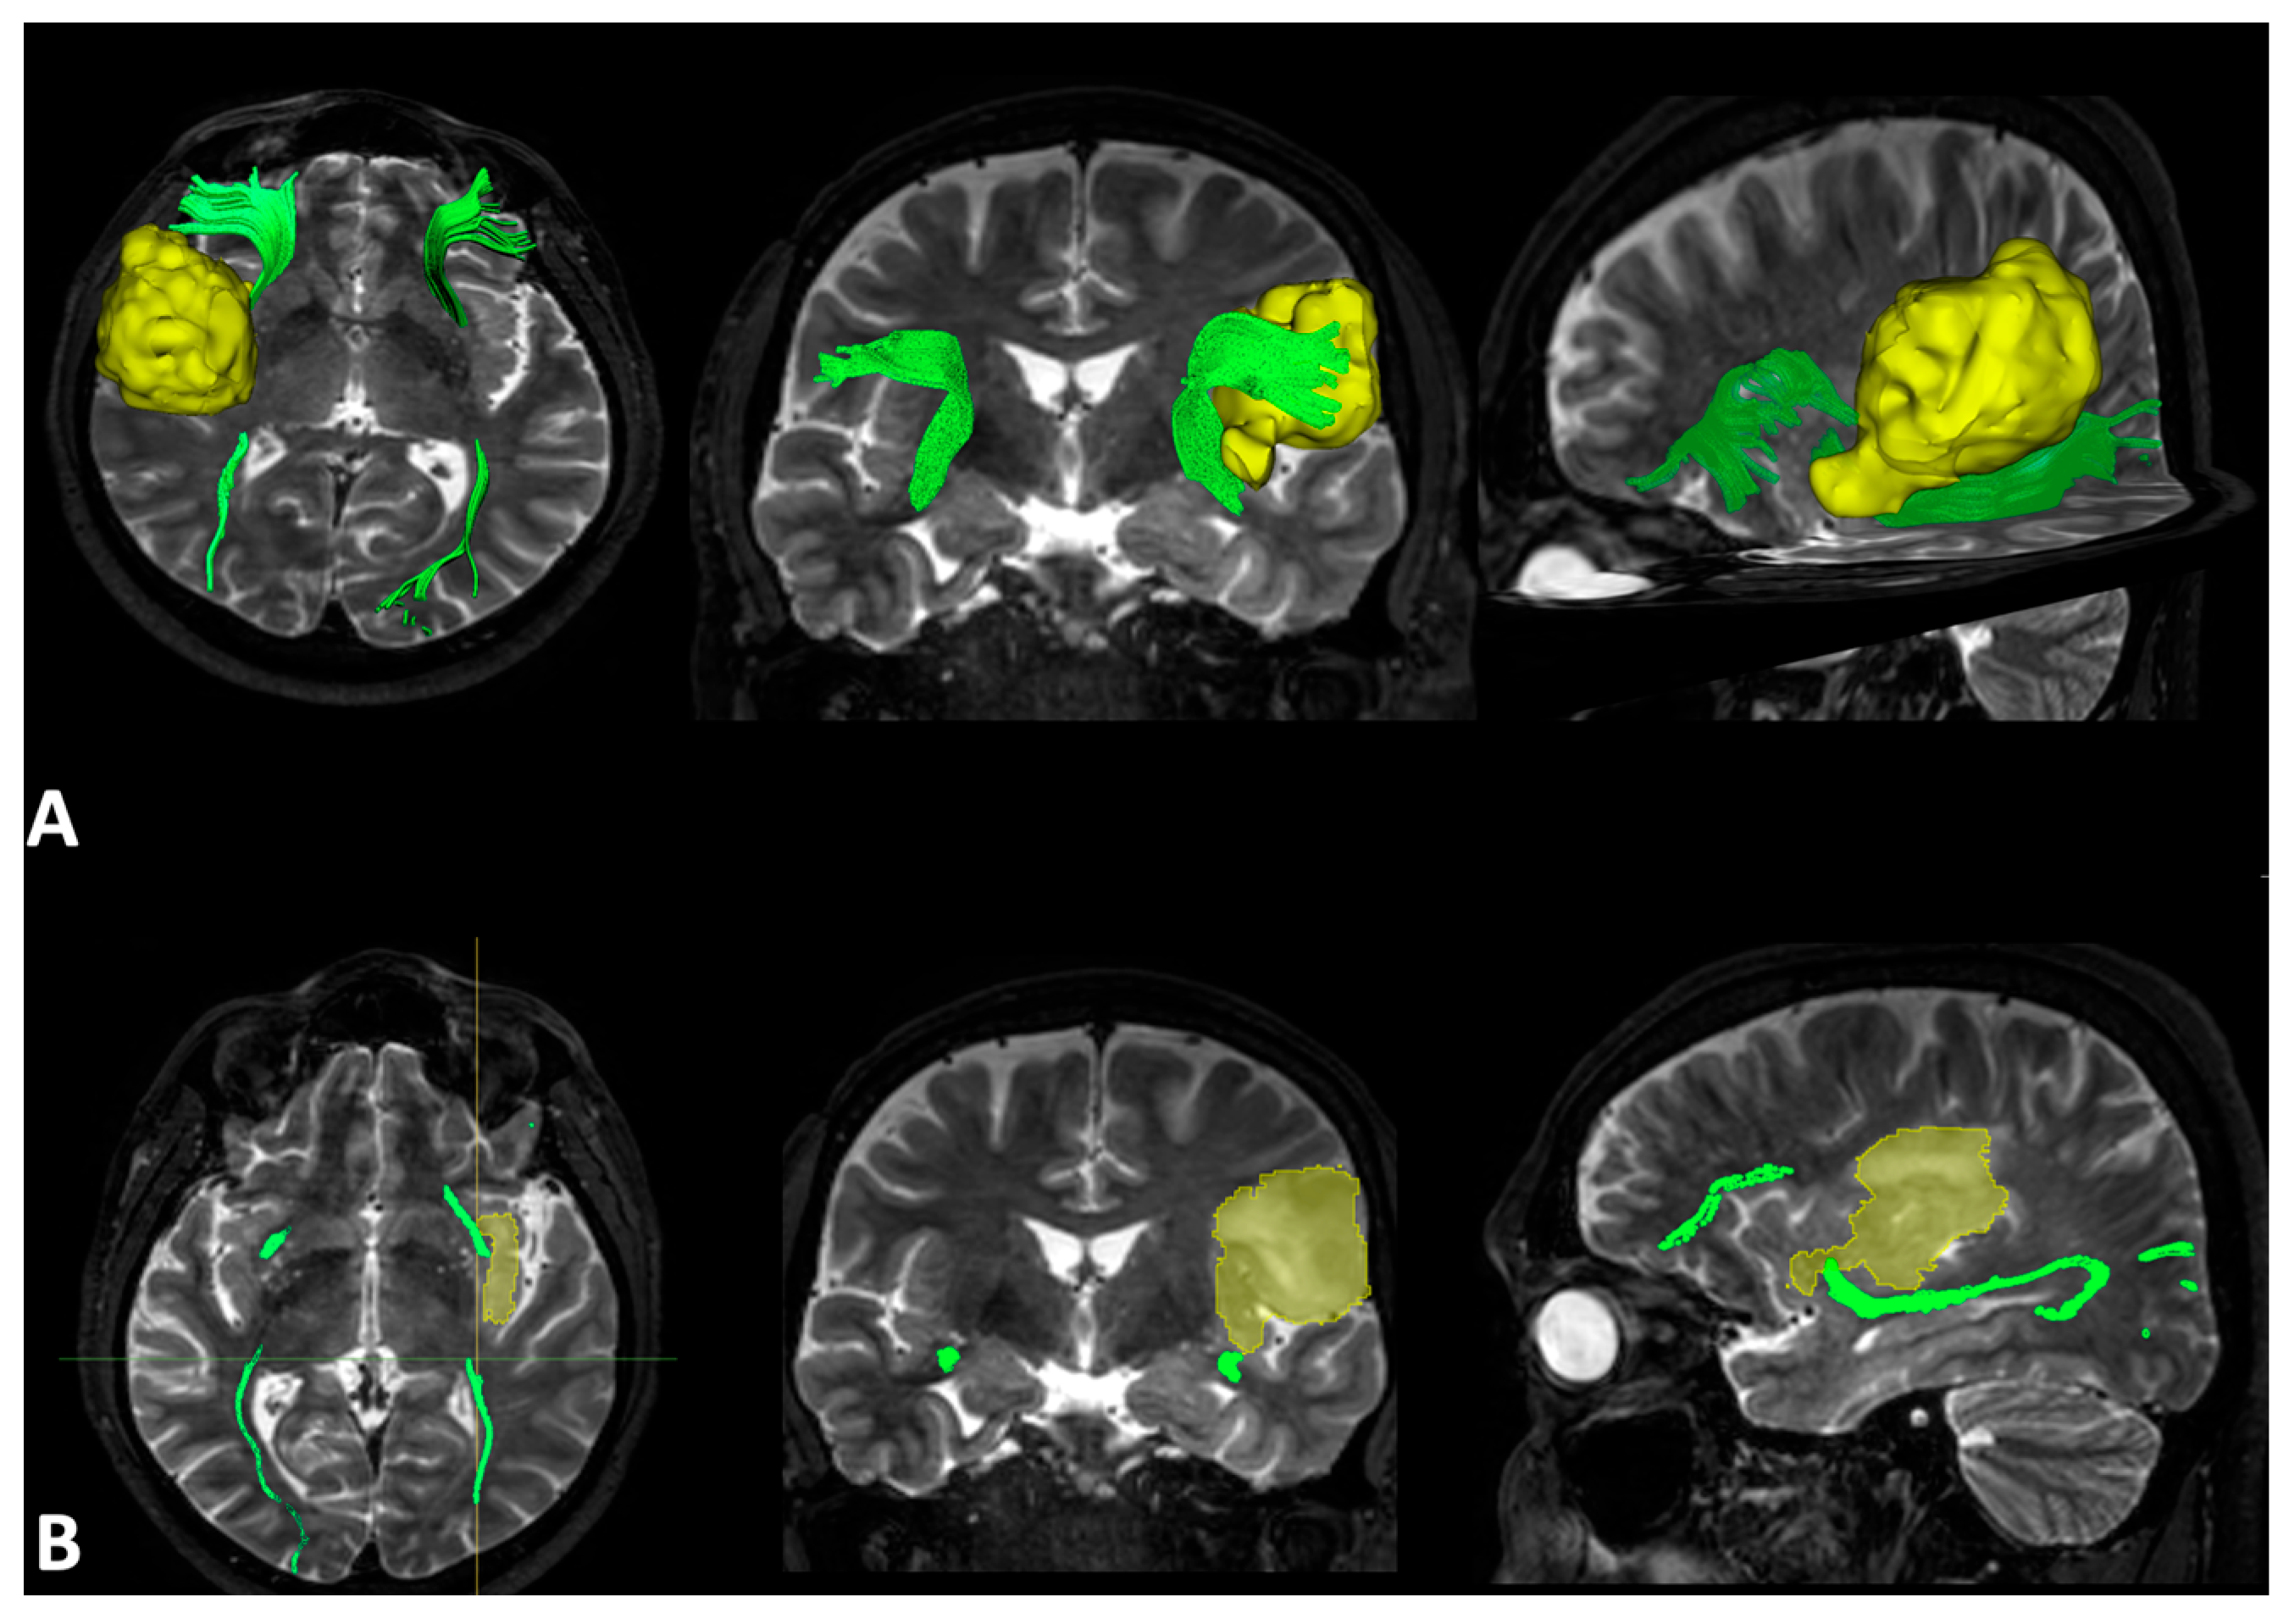

3.2. MRI Structural Data Analysis

3.4. DTI Quantitative and Qualitative Analysis